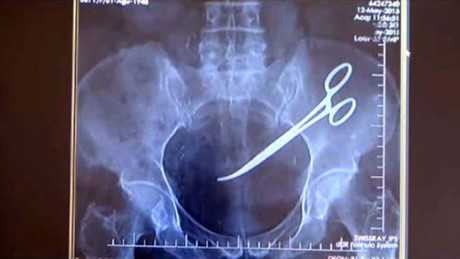

Bắc Kạn: Xác minh việc bác sĩ để quên kéo trong bụng bệnh nhân 18 năm

Bệnh viện Đa khoa tỉnh Bắc Kạn đang tiến hành xác minh việc bác sĩ phẫu thuật để quên chiếc kéo dài 15cm trong ổ bụng bệnh nhân từ 18 năm trước.